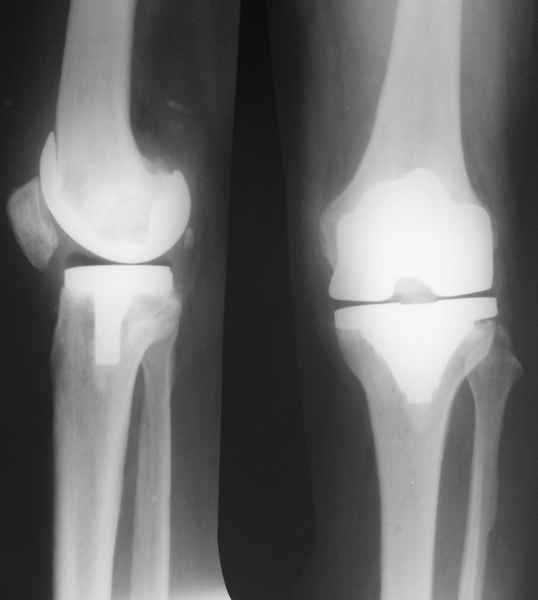

В феврале 2007 года пациентке выполнено эндопротезирование коленного сустава.

Есть вопросы к установке протеза.

Скорее всего тибиальное плато было не конца резецировано и в задненаружных отделах осталась ступенька. Это привело к тому, что тибиальный компонент завалился на варус.